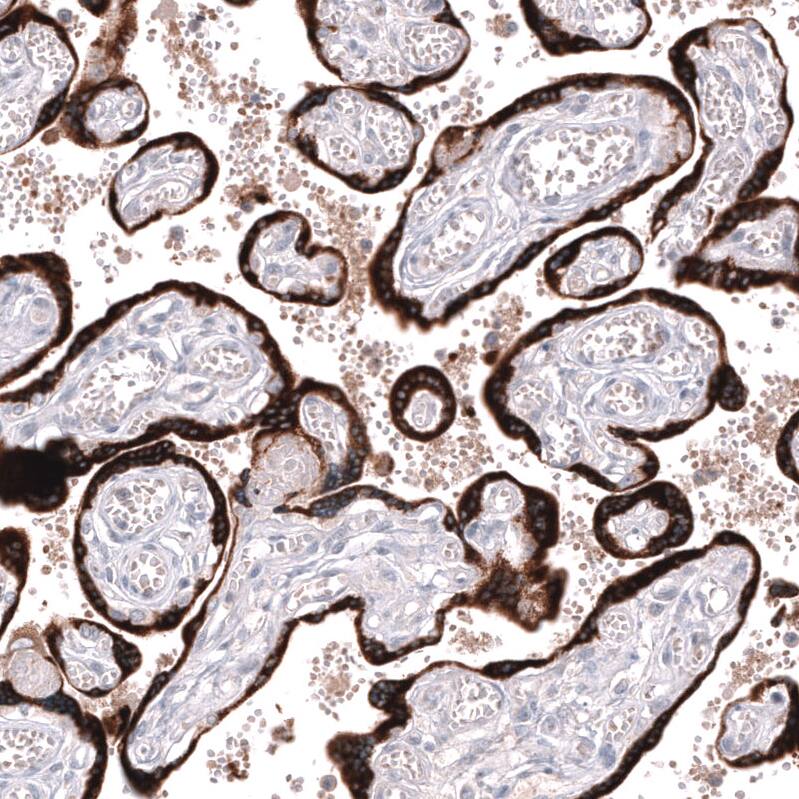

Orthogonal Strategies: Analysis in human placenta and kidney tissues using NBP3-44161 antibody. Corresponding Inhibin beta A RNA-seq data are presented for the same tissues.

Staining of human placenta shows strong cytoplasmic positivity in trophoblastic cells.